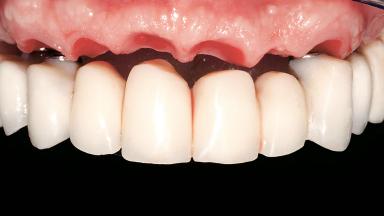

Immediate Loading of Six Implants in the Maxilla and Final Restoration with a Full-Arch CAD/CAM Zirconia FDP

A 63-year-old male patient was referred for a consultation and treatment of partial edentulism in the maxilla. The patient presented with residual anterior teeth and declined a partial removable prosthesis. He reported that the maxillary posterior teeth had been extracted due to mobility and periodontal disease two months before the consultation. The patient’s chief complaint was that his residual maxillary teeth were mobile and that he was unable to chew. The patient’s desire was a stable and comfortable fixed maxillary rehabilitation. The patient was a light smoker (fewer than 10 cigarettes/ day), and his medical history was without significant findings. He was not on any regular medication at the time of consultation. The extraoral examination revealed a normal physiognomy with a correct distribution of the facial thirds. The patient presented a low lip line, and the transition line between teeth and soft tissues was not exposed during a forced smile.

Abutment Type CAD/CAM

Prosthesis Type FDP

Lip Line No exposure of papillae Exposure of papillae Full exposure of mucosa margin

Defining Characteristics Fully edentulous upper jaw to be rehabilitated with an implant-borne fixed dental prosthesis